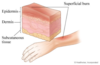

What structures are labelled in the diagram?

What is the role of the sebaceous glands?

they secrete sebum

one type is associated with the hair follicle and secretes sebum into the hair follicle

the other type secretes sebum directly onto the surface of the skin

What is the role of eccrine glands?

they have a thermoregulation function and produce sweat

they are the major sweat glands of the human body that are found in virtually all skin

they have the highest density in the palm and soles and lowest density on the trunk and extremities

What is the role of the apocrine glands?

apocrine glands in the skin and eyelid are sweat glands

most are found in the armpits, groin and area around the nipples

apocrine glands in the skin are scent glands and their secretions usually have an odour

What is the role of the arrector pili muscle?

it is a bundle of smooth muscle fibres

it inserts at one end into the follicle sheath just below the sebaceous glands and the other in the superficial dermis